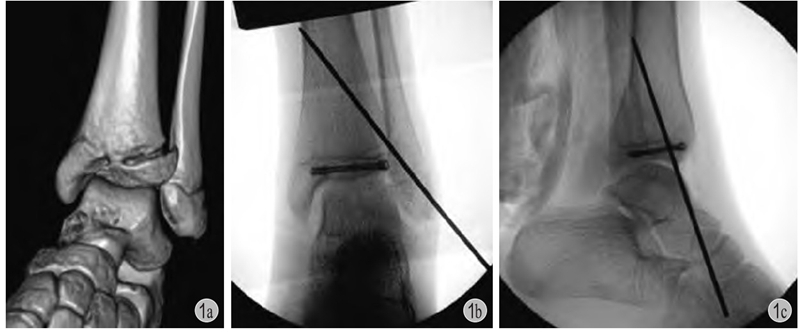

图1 患儿 女12岁

a:左胫骨远端三平面骨折;b、c:切开复位,空心钉+克氏针固定,空心钉平行骺板且位于骨骺内,辅以斜行克氏针穿越骺板固定